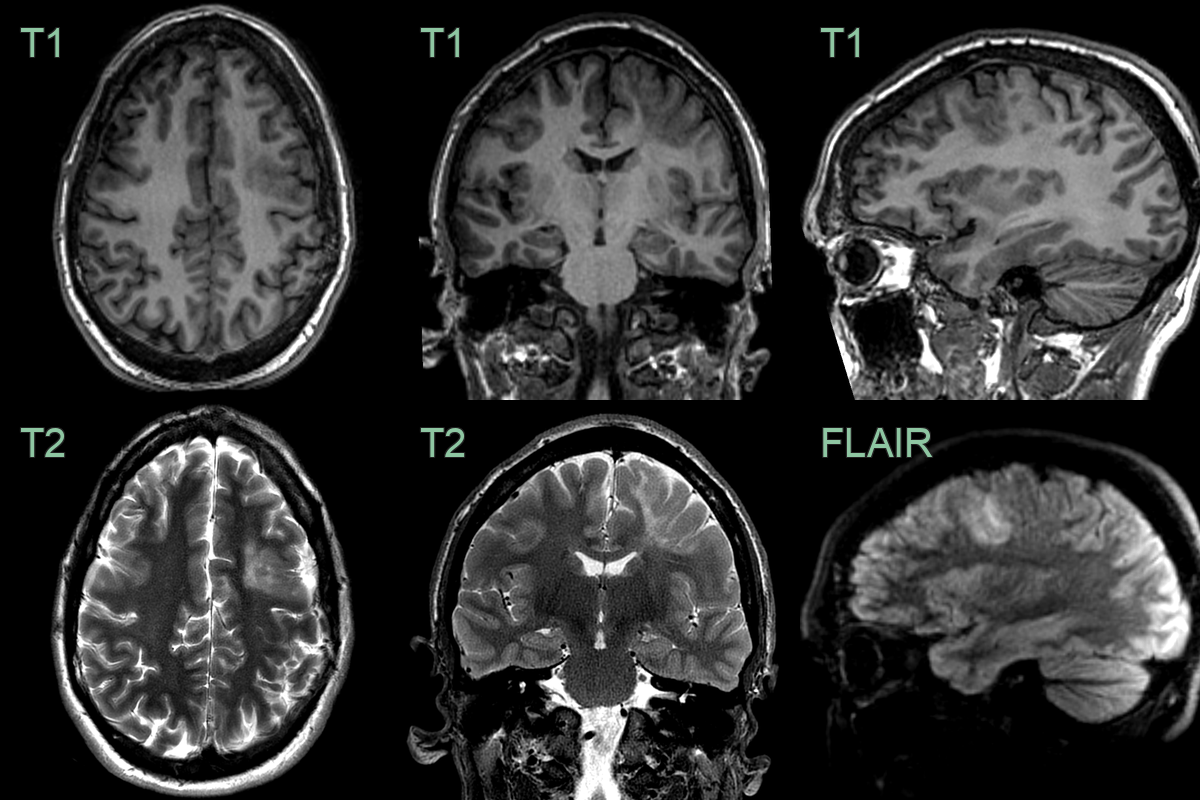

• 30-year-old patient with frontal lobe seizures.

• MRI showed a subtle region of cortical thickening at the depth of the inferior frontal sulcus.

• A hyperintense tail extending towards the lateral ventricle indicated a Type II focal cortical dysplasia.